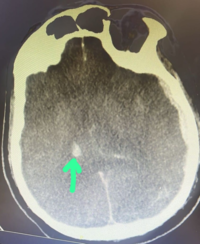

• NRBC

Najmaldin Saki, P...

Nucleated Red Blo...